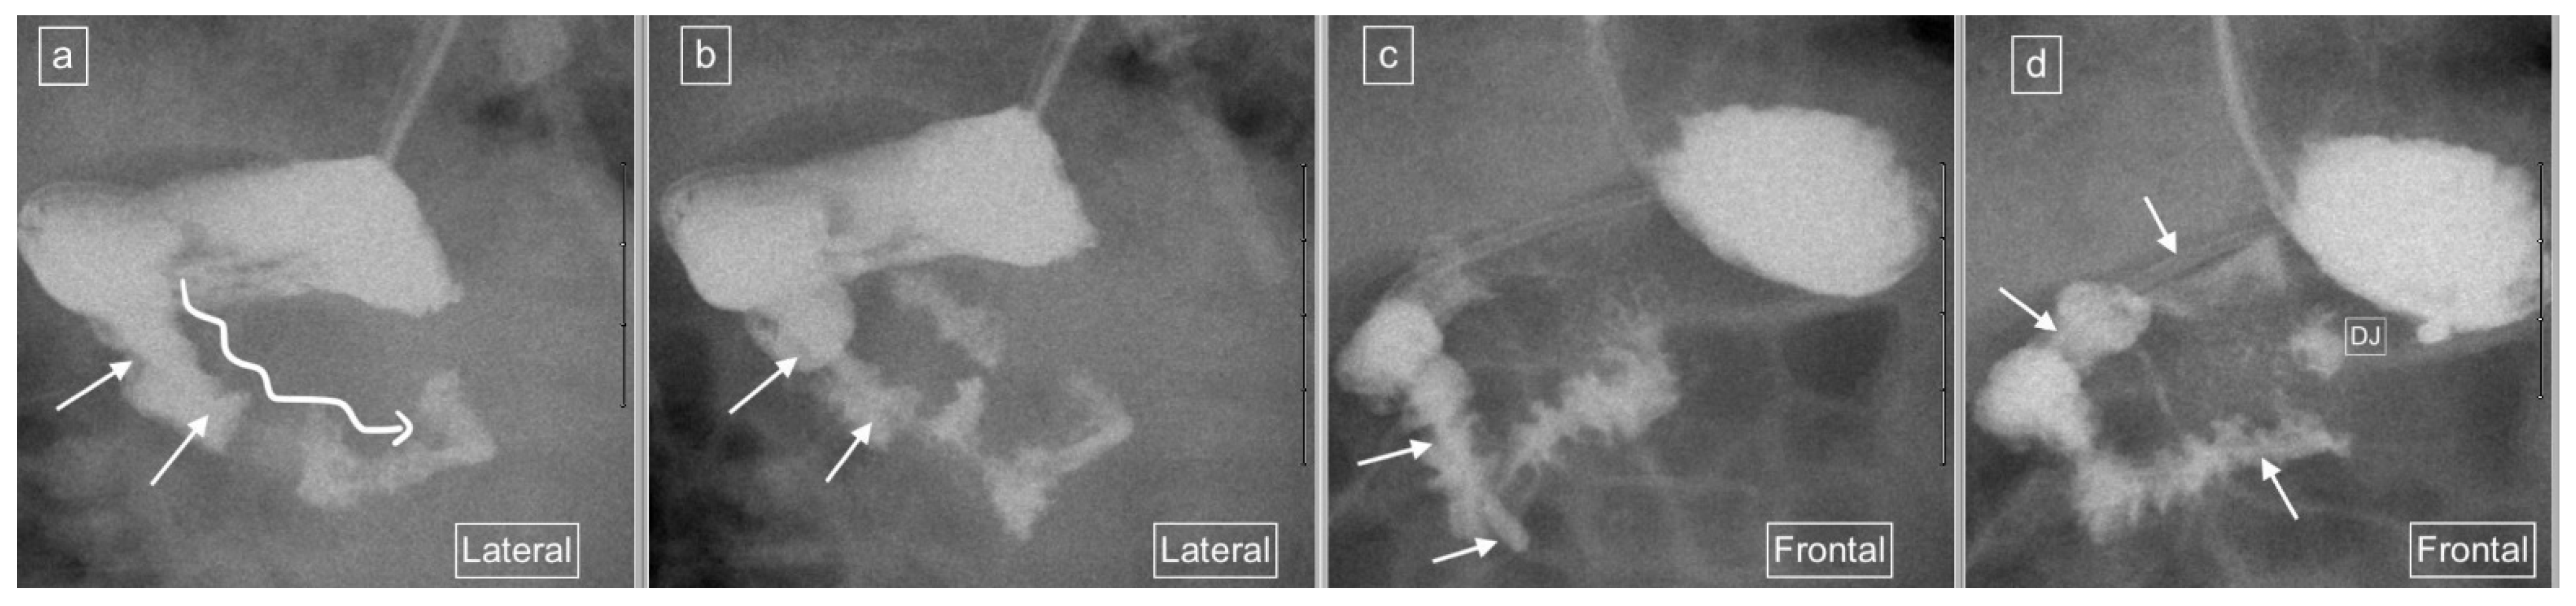

Figure 7.

Representative images captured during an UGIS in a 6-month-old girl showing an indwelling enteric tube with its tip terminating in the third part of the duodenum. (a) Early and (b) later lateral views captured, demonstrate what was interpreted as a descending staircase sign (long winding arrow) but actually represents distortion of the C-loop configuration with duodenal spasm due to the presence of the enteric tube (short arrows). (c,d) are representative frontal view image captures with a relatively normal C-loop configuration and a normal position of the duodeno-jejunal flexure (DJ). The enteric tube is seen within the duodenum (arrows).